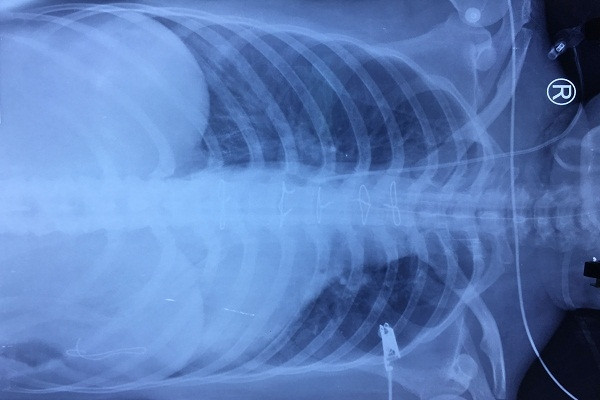

Kết quả chụp X-quang vùng ngực của bệnh nhân sau khi phẫu thuật - Ảnh: N.L

Bác sĩ Châu cho biết trên lâm sàng, các bác sĩ xác định ngay đây là vết thương thấu ngực sốc mất máu nặng, khả năng thủng tim rất cao, có thể kèm tổn thương ở ổ bụng, nguy cơ tử vong rất cao. Bệnh nhân được chuyển ngay vào phòng mổ tiến hành phẫu thuật khẩn cấp.